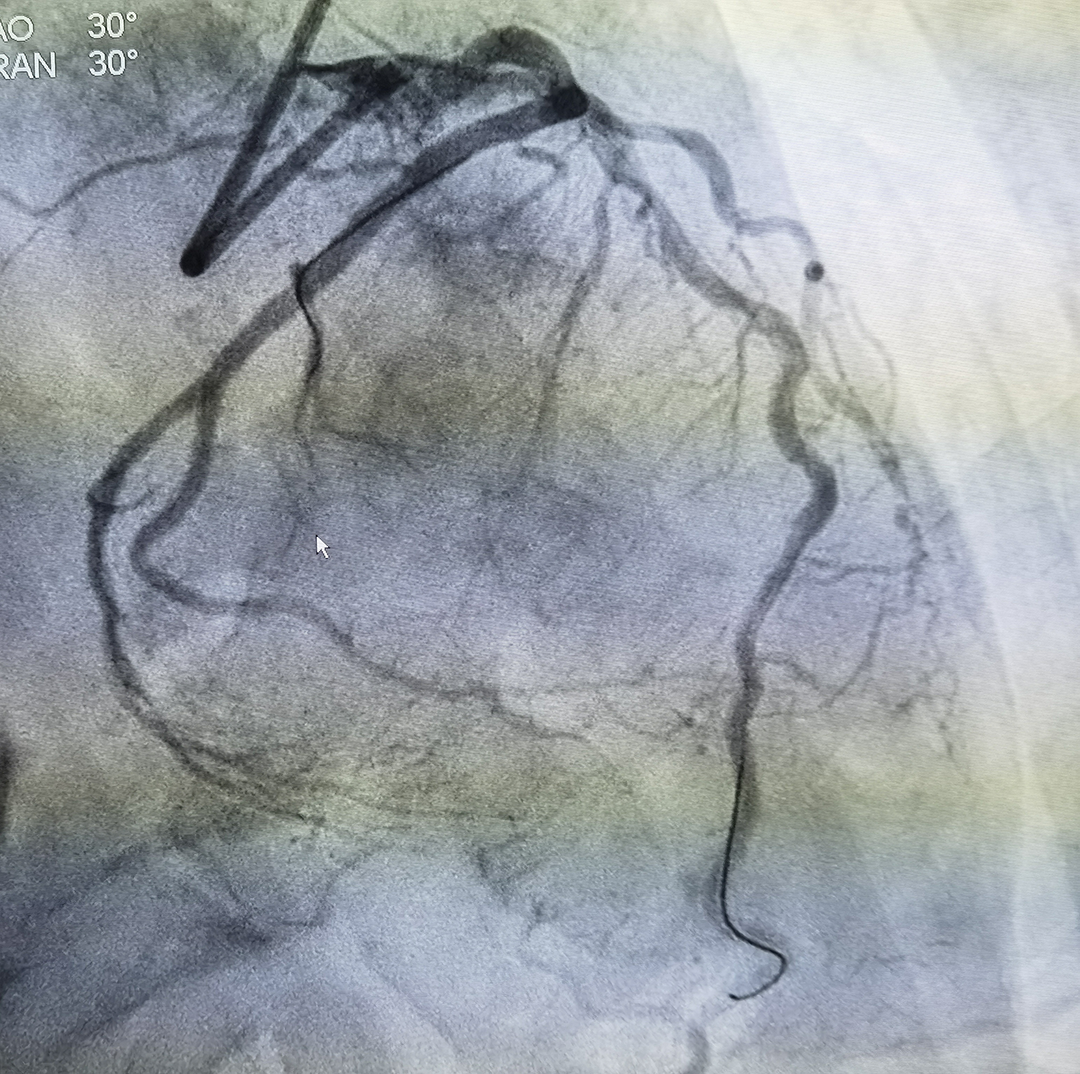

钙化病变明显改善

支架顺利通过病变并释放扩张、效果良好